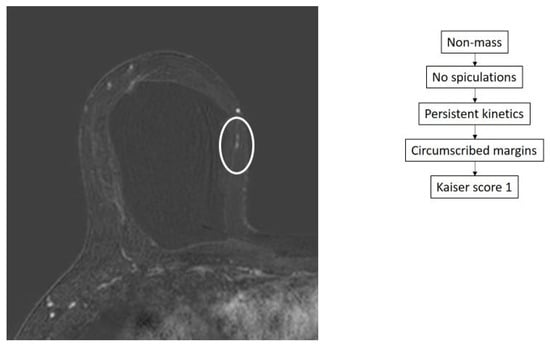

- Dietzel, M.; Baltzer, P.A.T. How to Use the Kaiser Score as a Clinical Decision Rule for Diagnosis in Multiparametric Breast MRI: A Pictorial Essay. Insights Imaging 2018, 9, 325–335. [Google Scholar] [CrossRef] [PubMed]